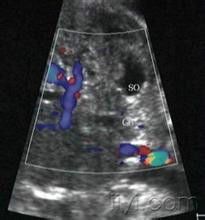

絕大多數持續性右臍靜脈不合併胎兒畸形,僅少數可能會合併胎兒畸形,例如腦積水,單臍動脈,短肢,房間隔缺損,室間隔缺損,主動脈縮窄,氣管食管瘺,尿道下裂,腎移位,內臟反位,腸鏇轉異常,無肛畸形等。 如果右臍靜脈直接與下腔靜脈或右心房,甚至髂靜脈相連,聲像圖上就不能顯示臍靜脈在肝內與靜脈導管相連,這樣靜脈導管根本就是缺如。仔細跟蹤臍靜脈,能發現異常的連線部位,彩超可幫助診斷。這種情況往往可合併多發性畸形,如房室通道、心律失常、單臍動脈、腎盂積水、腎缺如、脈絡膜囊腫、胸腔積液、半錐體、指趾異常等,甚至是染色體畸形。

單純持續性右臍靜脈,無其他部位異常,往往為良性變異,一般無礙,預後較好。一旦合併其他畸形,預後往往視畸形情況而定。因此,超聲發現持續性右臍靜脈,就應仔細檢查靜脈導管,跟蹤臍靜脈及靜脈導管的走向,了解其是否連線於下腔靜脈。同時也應仔細檢查其它部位。有畸形者需檢查染色體,若核型異常就應中止妊娠。